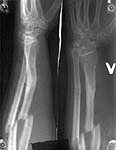

A female 30 y.o., right hand dominant, admitted at 4th post-injury day with a fracture of her left forearm. The forearm was fractured 7 years ago and treated non-operatively elsewhere.

A second fracture after a malunion does present the opportunity to try to correct the deformity from the original injury. I have done this for angulatory deformities when the second fracture is at or near the original injury. In this case the radius healed quite short (1.5cm) but only angulated a few degrees and now there is a radius, ulna shaft fracture more proximally. One could consider purposefuly shortening the ulna shaft fracture and plating both radius and ulna to end up with an ulna and radius of equal length but both short. However, ulna shortening is harder to accomplish than it would seem.

Your external fixation techniques offer the potential for lengthening the radius through the fracture which I suspect you are considering. Theoretically it should work although the DRUJ won't ever be normal.